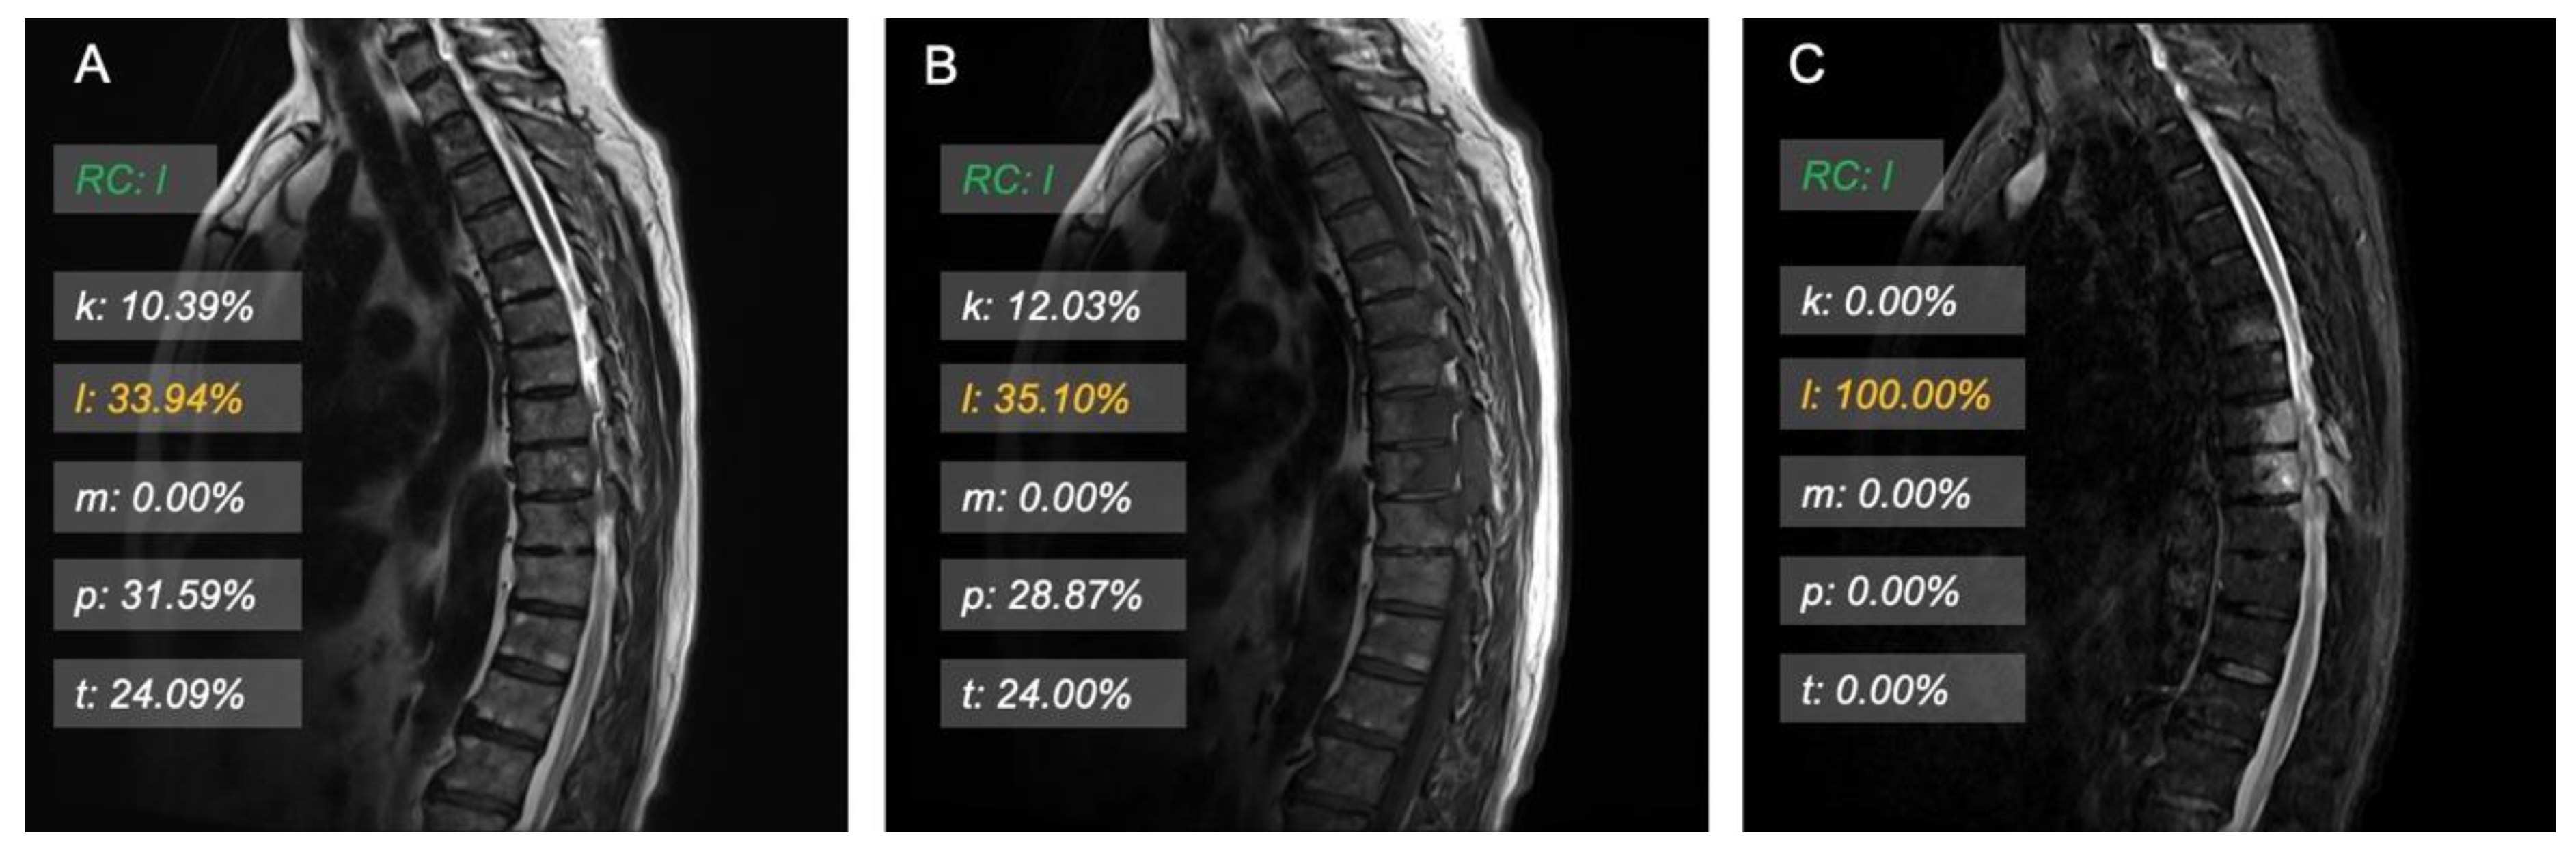

3.3. Model Interpretation and Examples